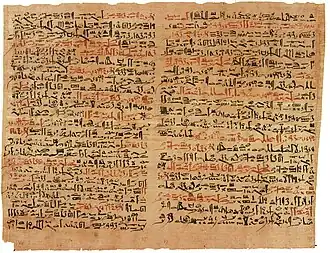

History

Spinal cord injury has been known to be devastating for millennia; the ancient Egyptian Edwin Smith Papyrus from 2500 BC, the first known description of the injury, says it is "not to be treated".[153] Hindu texts dating back to 1800 BC also mention SCI and describe traction techniques to straighten the spine.[153] The Greek physician Hippocrates, born in the fifth century BC, described SCI in his Hippocratic Corpus and invented traction devices to straighten dislocated vertebrae.[154] But it was not until Aulus Cornelius Celsus, born 30 BC, noted that a cervical injury resulted in rapid death that the spinal cord itself was implicated in the condition.[153] In the second century AD the Greek physician Galen experimented on monkeys and reported that a horizontal cut through the spinal cord caused them to lose all sensation and motion below the level of the cut.[155] The seventh-century Greek physician Paul of Aegina described surgical techniques for treatment of broken vertebrae by removing bone fragments, as well as surgery to relieve pressure on the spine.[153] Little medical progress was made during the Middle Ages in Europe; it was not until the Renaissance that the spine and nerves were accurately depicted in human anatomy drawings by Leonardo da Vinci and Andreas Vesalius.[155]